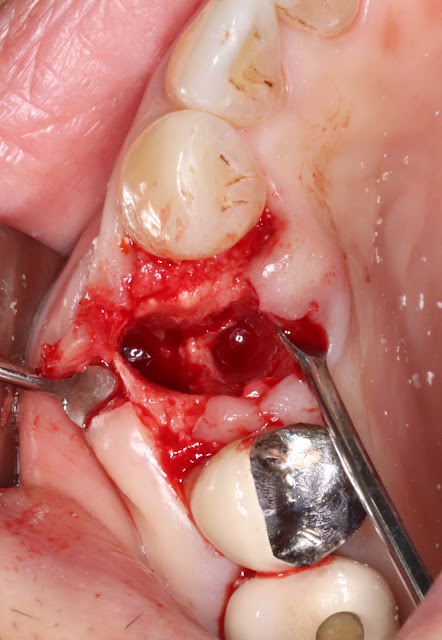

The final drilling was performed on the palatal side of the tooth.

I usually use a Taper drill and perform under-drilling by about one size. The length of the drill goes beyond the root, typically around 13mm.

If necessary, I also check whether the tooth has been completely extracted using a standard X-ray before implant placement.

Afterward, I proceed with the final drilling and then place the implant.